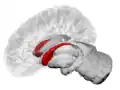

Caudate nucleus within the skull

Together with the putamen, the caudate forms the dorsal striatum, which is considered a single functional structure; anatomically, it is separated by a large white matter tract, the internal capsule, so it is sometimes also referred to as two structures: the medial dorsal striatum (the caudate) and the lateral dorsal striatum (the putamen). In this vein, the two are functionally distinct not as a result of structural differences, but merely due to the topographical distribution of function.

The caudate nuclei are located near the center of the brain, sitting astride the thalamus. There is a caudate nucleus within each hemisphere of the brain. Individually, they resemble a C-shape structure with a wider "head" (caput in Latin) at the front, tapering to a "body" (corpus) and a "tail" (cauda). Sometimes a part of the caudate nucleus is referred to as the "knee" (genu).[7] The caudate head receives its blood supply from the lenticulostriate artery while the tail of the caudate receives its blood supply from the anterior choroidal artery.[8]